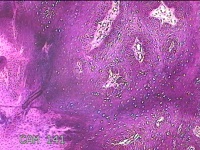

右侧中指皮下结节

性别

女

年龄

21岁

临床诊断

皮下结节

一般病史

发现右侧中指皮下结节1年余,无明显疼痛及不适。

标本名称

大体所见

灰白暗红色结节0.7x0.5x0.3cm一个,表面糜烂。